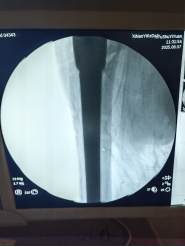

植入特制加长股骨柄假体,像"钢筋"一样牢牢固定新关节。

3小时后,手术圆满成功! 术中出血量控制理想,老人生命体征平稳。更让人惊喜的是,术后第二天邱婆婆就能自主屈伸双腿,疼痛明显缓解。"没想到还能再站起来!"家属紧握医生的手连连道谢。